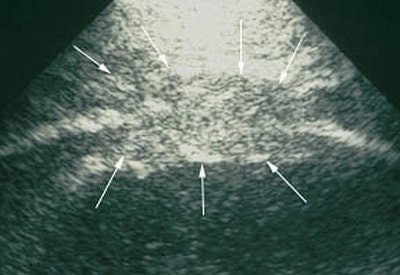

| Mesothelioma on ultrasound. Images courtesy of Dr. Felix Herth. |

"Pleural mesothelioma presents sonographically as an irregularly limited, echo-poor, knotty, or planar widening along the pleura," Herth wrote in Lung Cancer. "An increase in the pleural thickness, however, suggests the likelihood of malignancy. A widening of the pleura of more than 1 cm is considered highly indicative of the presence of malignant tumor" (August 2004, Vol. 45:1 supplement, pp. S63-67).